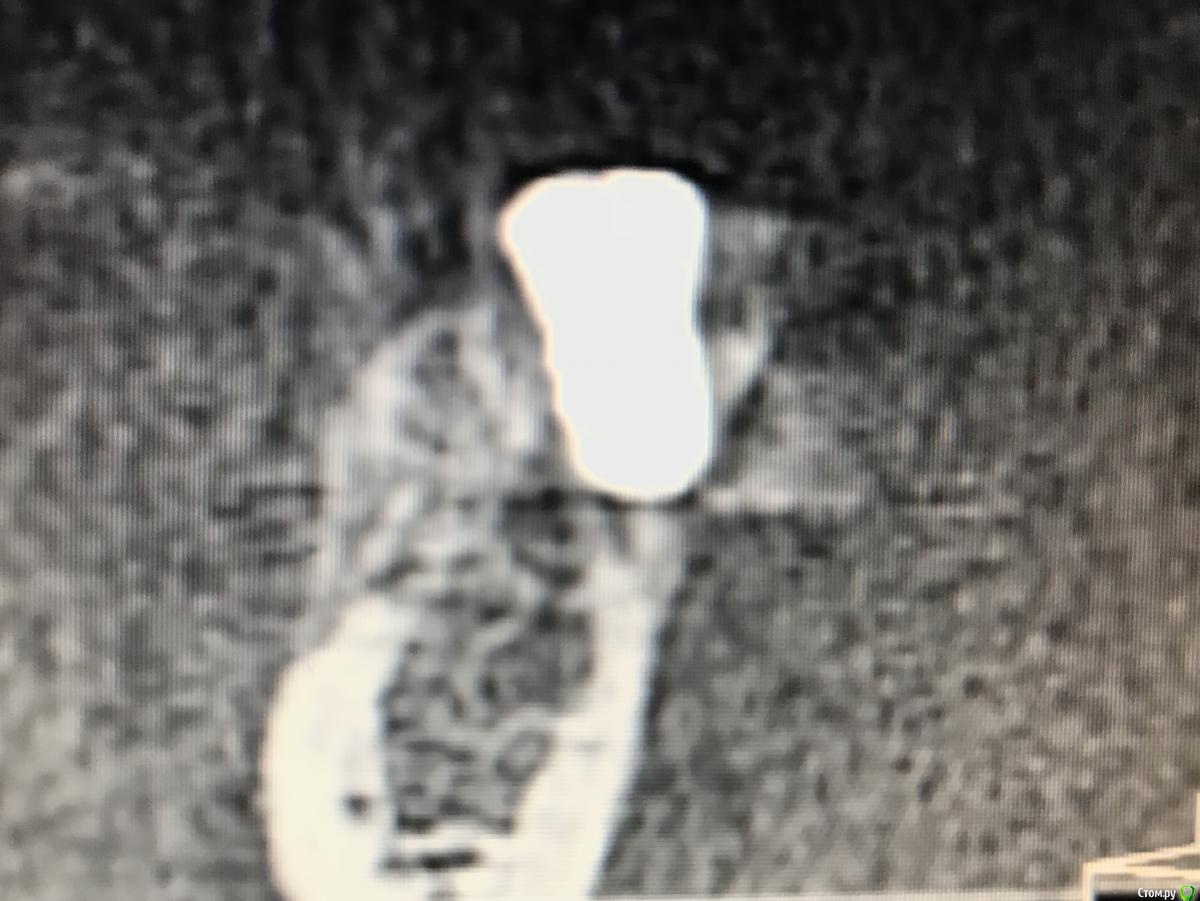

Kostoprav Опубликовано 21 декабря, 2018 Поделиться Опубликовано 21 декабря, 2018 Поделитесь опытом. Какой был графт,какой доступ,условия? На каком этапе заметили неудачу? С чем связываете? Какой срок наблюдения?графт остеобиол+ i prf . доступ аналогичный как у автора темы, использовал данную методику в боковых отделах нижней и верхней челюстях. из 6 пациентов только у двоих я получил прирост и то в одном случае результат был на троечку.неудачу замечал на этапе компьютерной томографии через 6 мес- отсутствие прироста кости либо графт просто "не прирастал" к кости ,а инкапсулировался в слизистой ( кт прилагается ). неудачи связываю с нестабильностью графта и возможно были повреждения периоста при его отслойке как следствие прорастание мягких тканей в графт. Ссылка на комментарий

колесников Опубликовано 22 декабря, 2018 Автор Поделиться Опубликовано 22 декабря, 2018 Я бы не назвал это неудачей,аугментат довольно плотно контактирует с кортикалкой. Мне кажется вы слишком низко отслоились,должна получится округлая сосиска. Я отслаиваю коронально,затем моделирую нужной формы. 1 Ссылка на комментарий

kladoffka Опубликовано 14 марта, 2019 Поделиться Опубликовано 14 марта, 2019 Вопрос в том, стало ли это костью? Делал как то сосидж, через 6 месяцев на кт все отлично, а при и раскрытии материал так и лежал поверх кости и поднялся вместе с периостом Ссылка на комментарий

колесников Опубликовано 14 марта, 2019 Автор Поделиться Опубликовано 14 марта, 2019 (изменено) Это аллографт,не ксено. Если он интегрирован -он есть,если не интегрирован,не имеет контакта с нативной костью-он лизируется. Это ксерографт может инкапсулироваться и оставаться рентгеноконтрастным. Изменено 14 марта, 2019 пользователем колесников 1 Ссылка на комментарий